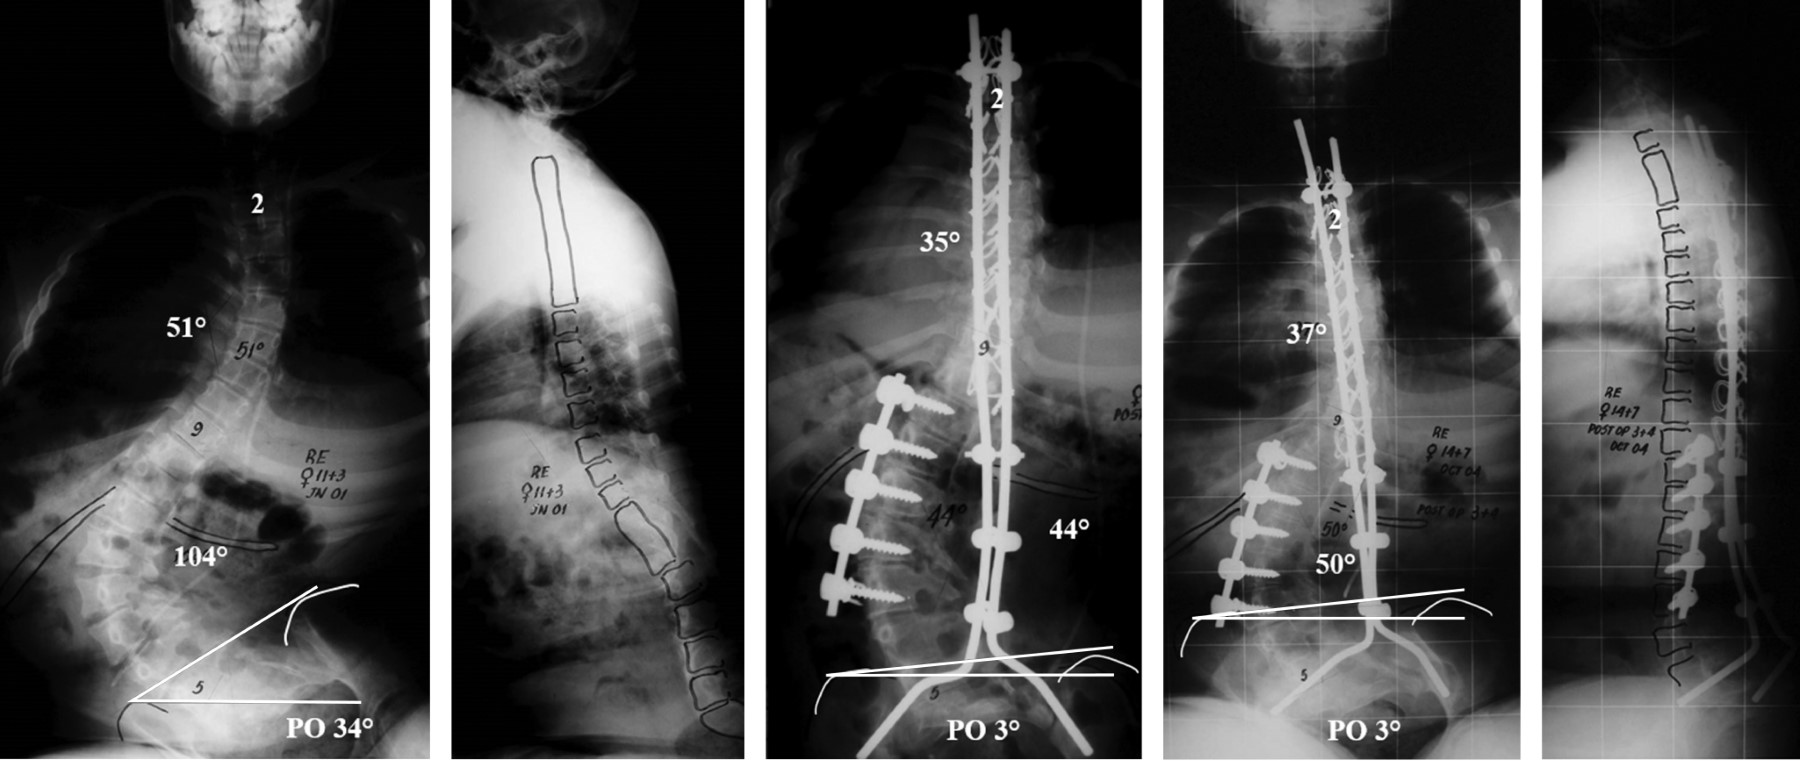

Objective: The aim of the study was to evaluate the outcomes and complications in patients with myelomeningocele who have undergone spinal fusion for neuromuscular scoliosis. Material and methods: Retrospective study of 40 consecutive patients with myelomeningocele with neuromuscular scoliosis who underwent spinal arthrodesis, treated at our center between July 1991 and July 2028. Results: Mean follow up was 10 years. There were 19 male and 21 females. The average age at operation was 13 years. The mean preoperative scoliosis curve was 90o. At last follow up, the mean scoliosis curve was 43o. Mean correction of 52%. The average of pelvic obliquity was 19o. At last follow up de obliquity was 9o. Mean correction of 53%. The mean preoperative coronal balance was 28.4 mm. At the last follow up it was 17 mm. Mean correction of 40%. The mean preoperative kyphosis was 50o. At the last follow up it was 41o. Mean correction of 18%. The mean preoperative sagittal balance was 63.3 mm. At the last follow up it was 38.3 mm. Mean correction of 40%. There were 13 complications (32.5%), with infection being the most frequently observed complication. Conclusions: The goals of the spinal surgery in patients with MMC are to obtain a stable, balanced and painless spinal fusion. Although the surgical treatment of these patients remains difficult, it is associated with high complication rate.

Figure 2